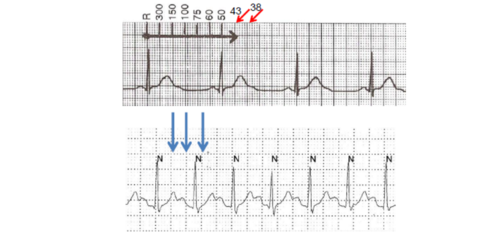

| Benefits of multiple leads | |

| What is this? | Point is sometimes you need more then one lead |